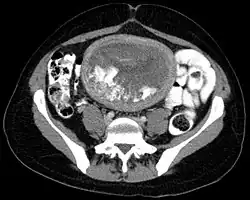

The diagnosis is strongly suggested by ultrasound (sonogram), but definitive diagnosis requires histopathological examination. On ultrasound, the mole resembles a bunch of grapes ("cluster of grapes" or "honeycombed uterus" or "snow-storm").[14] There is increased trophoblast proliferation and enlarging of the chorionic villi, and angiogenesis in the trophoblasts is impaired.[15]